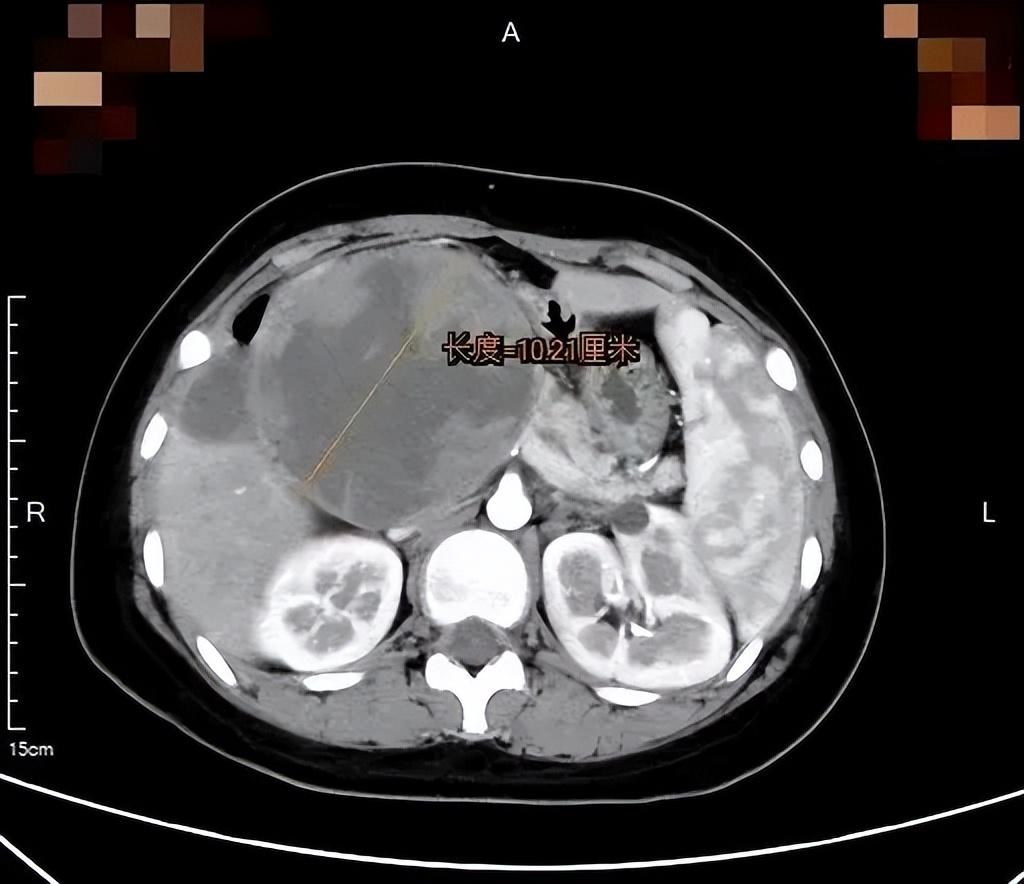

增强CT检查显示,一个直径10cm的肿瘤像狰狞的章鱼,触须般的包膜紧紧缠绕着小微的胰头部位,将十二指肠压成了“纸片”,消化道完全梗阻,肿瘤内部甚至出现渗血。胰腺外科王伟珅副主任医师为小微立即联系开通绿色通道,当天收治入院。

“这是胰腺实性假乳头状瘤,虽然属于低度恶性,但长在这个位置很凶险。”胰腺外科许志伟副主任医师解释道,胰头被十二指肠环抱,后方紧贴着门静脉和肠系膜血管,巨大的肿瘤在胰头这个“交通枢纽”位置,不仅压迫胆总管、胰管,还侵蚀了十二指肠乳头,就像卡住的巨石,阻断了消化液流动,还随时可能引发致命性出血或感染。更危险的是影像上可见肿瘤内部散在的出血点,意味着巨瘤随时可能破裂,情况十分危急。